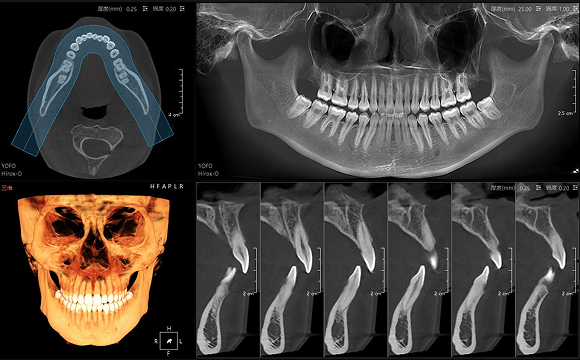

• CT

CT

• 3D全景

數字全景

• 3D 正側位

3D 正側位

• 3D TMJ視圖

3D TMJ視圖

16×15cm

非拼接大視野

28lp/cm

高精準